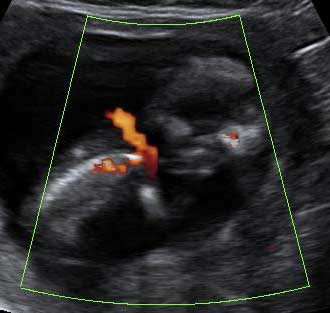

Esta ecografía en rotación muestra un embarazo gemelar de 12 semanas. La imagen en tres dimensiones muestra claramente dos fetos en sus respectivos sacos amnióticos. La membrana de separación entre ambas bolsas es bastante gruesa. Como la separación es muy clara, eso quiere decir que además de dos bolsas, existen dos placentas. Una de ellas se aprecia en la parte inferior izquierda de la cavidad uterina.